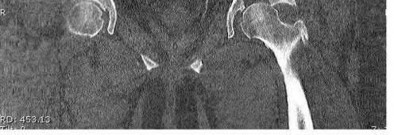

Figures A-C are the radiographs of a 26-year-old male who presents to the emergency department following a motocross accident. Two attempts at a closed reduction by the on-call orthopedic resident were unsuccessful. Figures D and E are the pre-operative axial CT-images that were obtained. The patient undergoes surgical fixation seen in Figure F. Limitations in post-operative dorsiflexion is likely influenced by which of the following?

Figures A-C: The initial radiographs reveal the posterior subluxation of the talus with associated posterior subluxation of the fibula without significant coronal plane deformity. This deformity should raise the suspicion of a Bosworth fracture-dislocation, especially if closed reduction is not successful. Figures D and E: Axial CT images demonstrating Bosworth fracture-dislocation of the fibula entrapped behind the tibia. Also, note the fracture extension to the posteromedial rim in this posterior pilon variant.